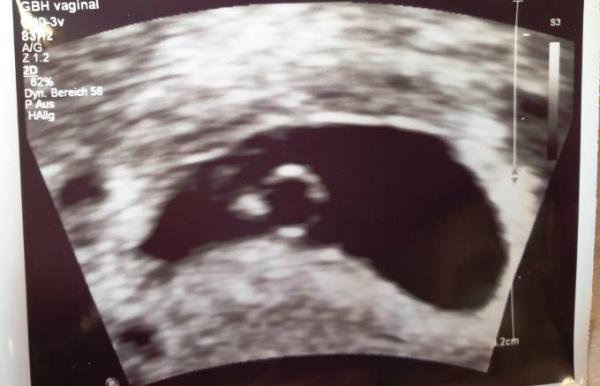

Für mich immer noch nicht wirklich zu glauben, hatte ich dann am Mittwoch das erste Ultraschallbild in der Hand (vor Stolz möchte ich es euch natürlich nicht verheimlichen). Ich freue mich sehr auf die nächste Zeit und bin mir sicher, dass es hier viele gute Tipps geben wird und hoffe natürlich, dass meine Schwangerschaft weiterhin positiv verläuft . Bis jetzt habe ich nur leichte Übelkeit, dafür aber einen Blähbauch mit einem momentan leichten Druck im Unterbauch beim sitzen, vielleicht sollte ich doch lieber ins Bett gehen - wo ich momentan nichts dagegen hätte